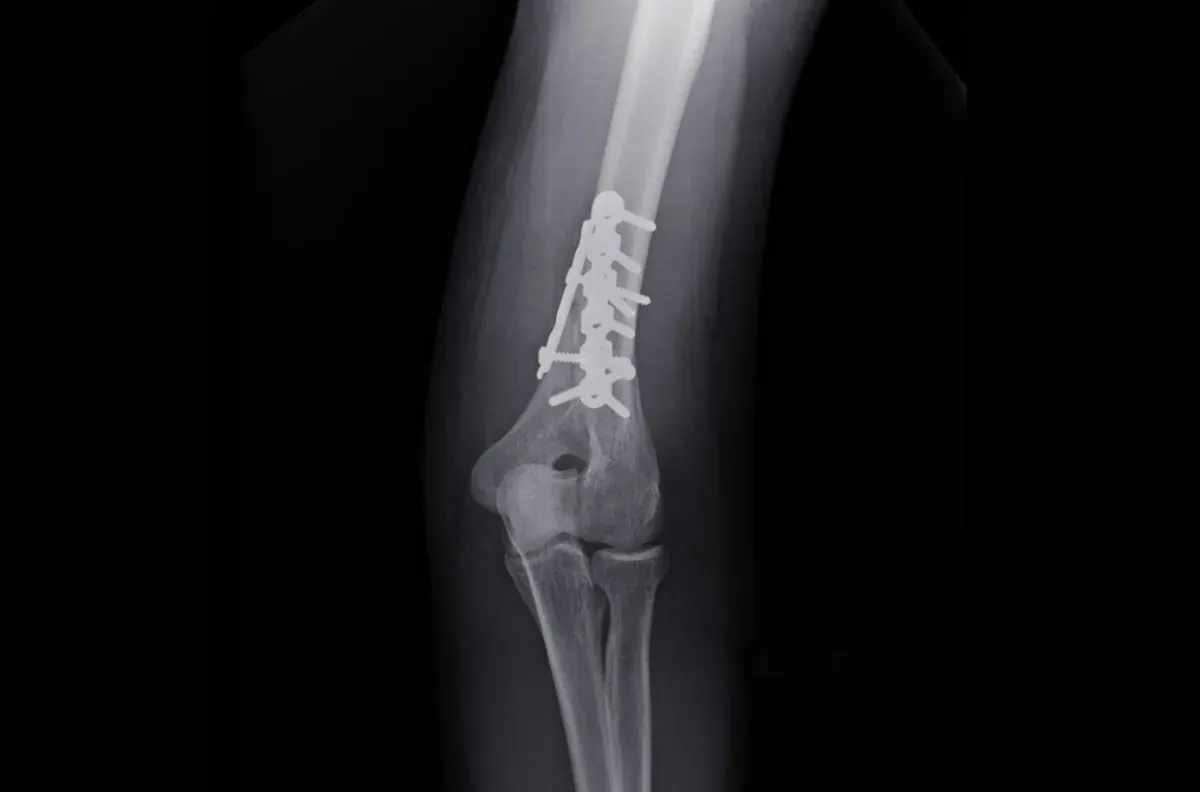

Wybór metody leczenia czy będzie to leczenie zachowawcze z unieruchomieniem w ortezie lub gipsie, czy też operacja z zespoleniem kości płytką lub gwoździem śródszpikowym ma fundamentalne znaczenie dla harmonogramu rehabilitacji. Po leczeniu zachowawczym, często trzeba dłużej czekać na pełne obciążenie i rozpoczęcie intensywnych ćwiczeń, aby nie zakłócić zrostu kostnego. Z kolei po operacji, dzięki stabilizacji odłamów, rehabilitację można zazwyczaj rozpocząć wcześniej, często już 2-3 dni po zabiegu, co jest kluczowe dla zapobiegania sztywności i zanikom mięśniowym. Oczywiście, intensywność ćwiczeń jest początkowo bardzo kontrolowana.